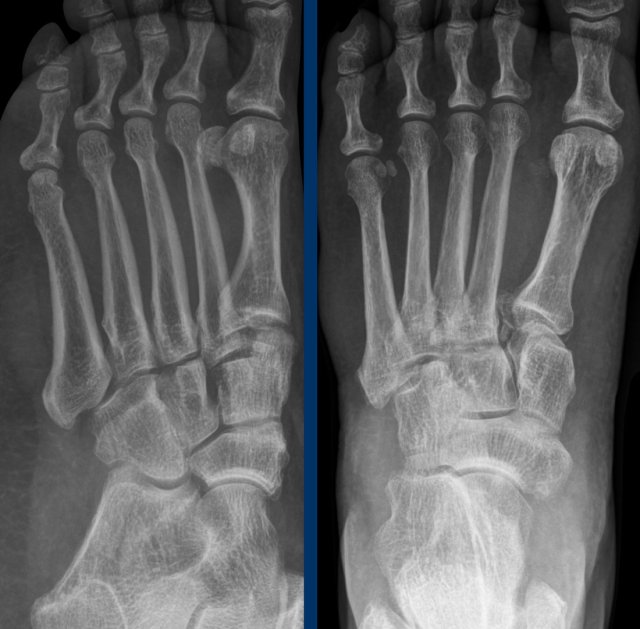

case 2 - chronic pain

17 year old girl with chronic pain in ankle and foot.

She had recurrent ankle sprains.

What are the findings?